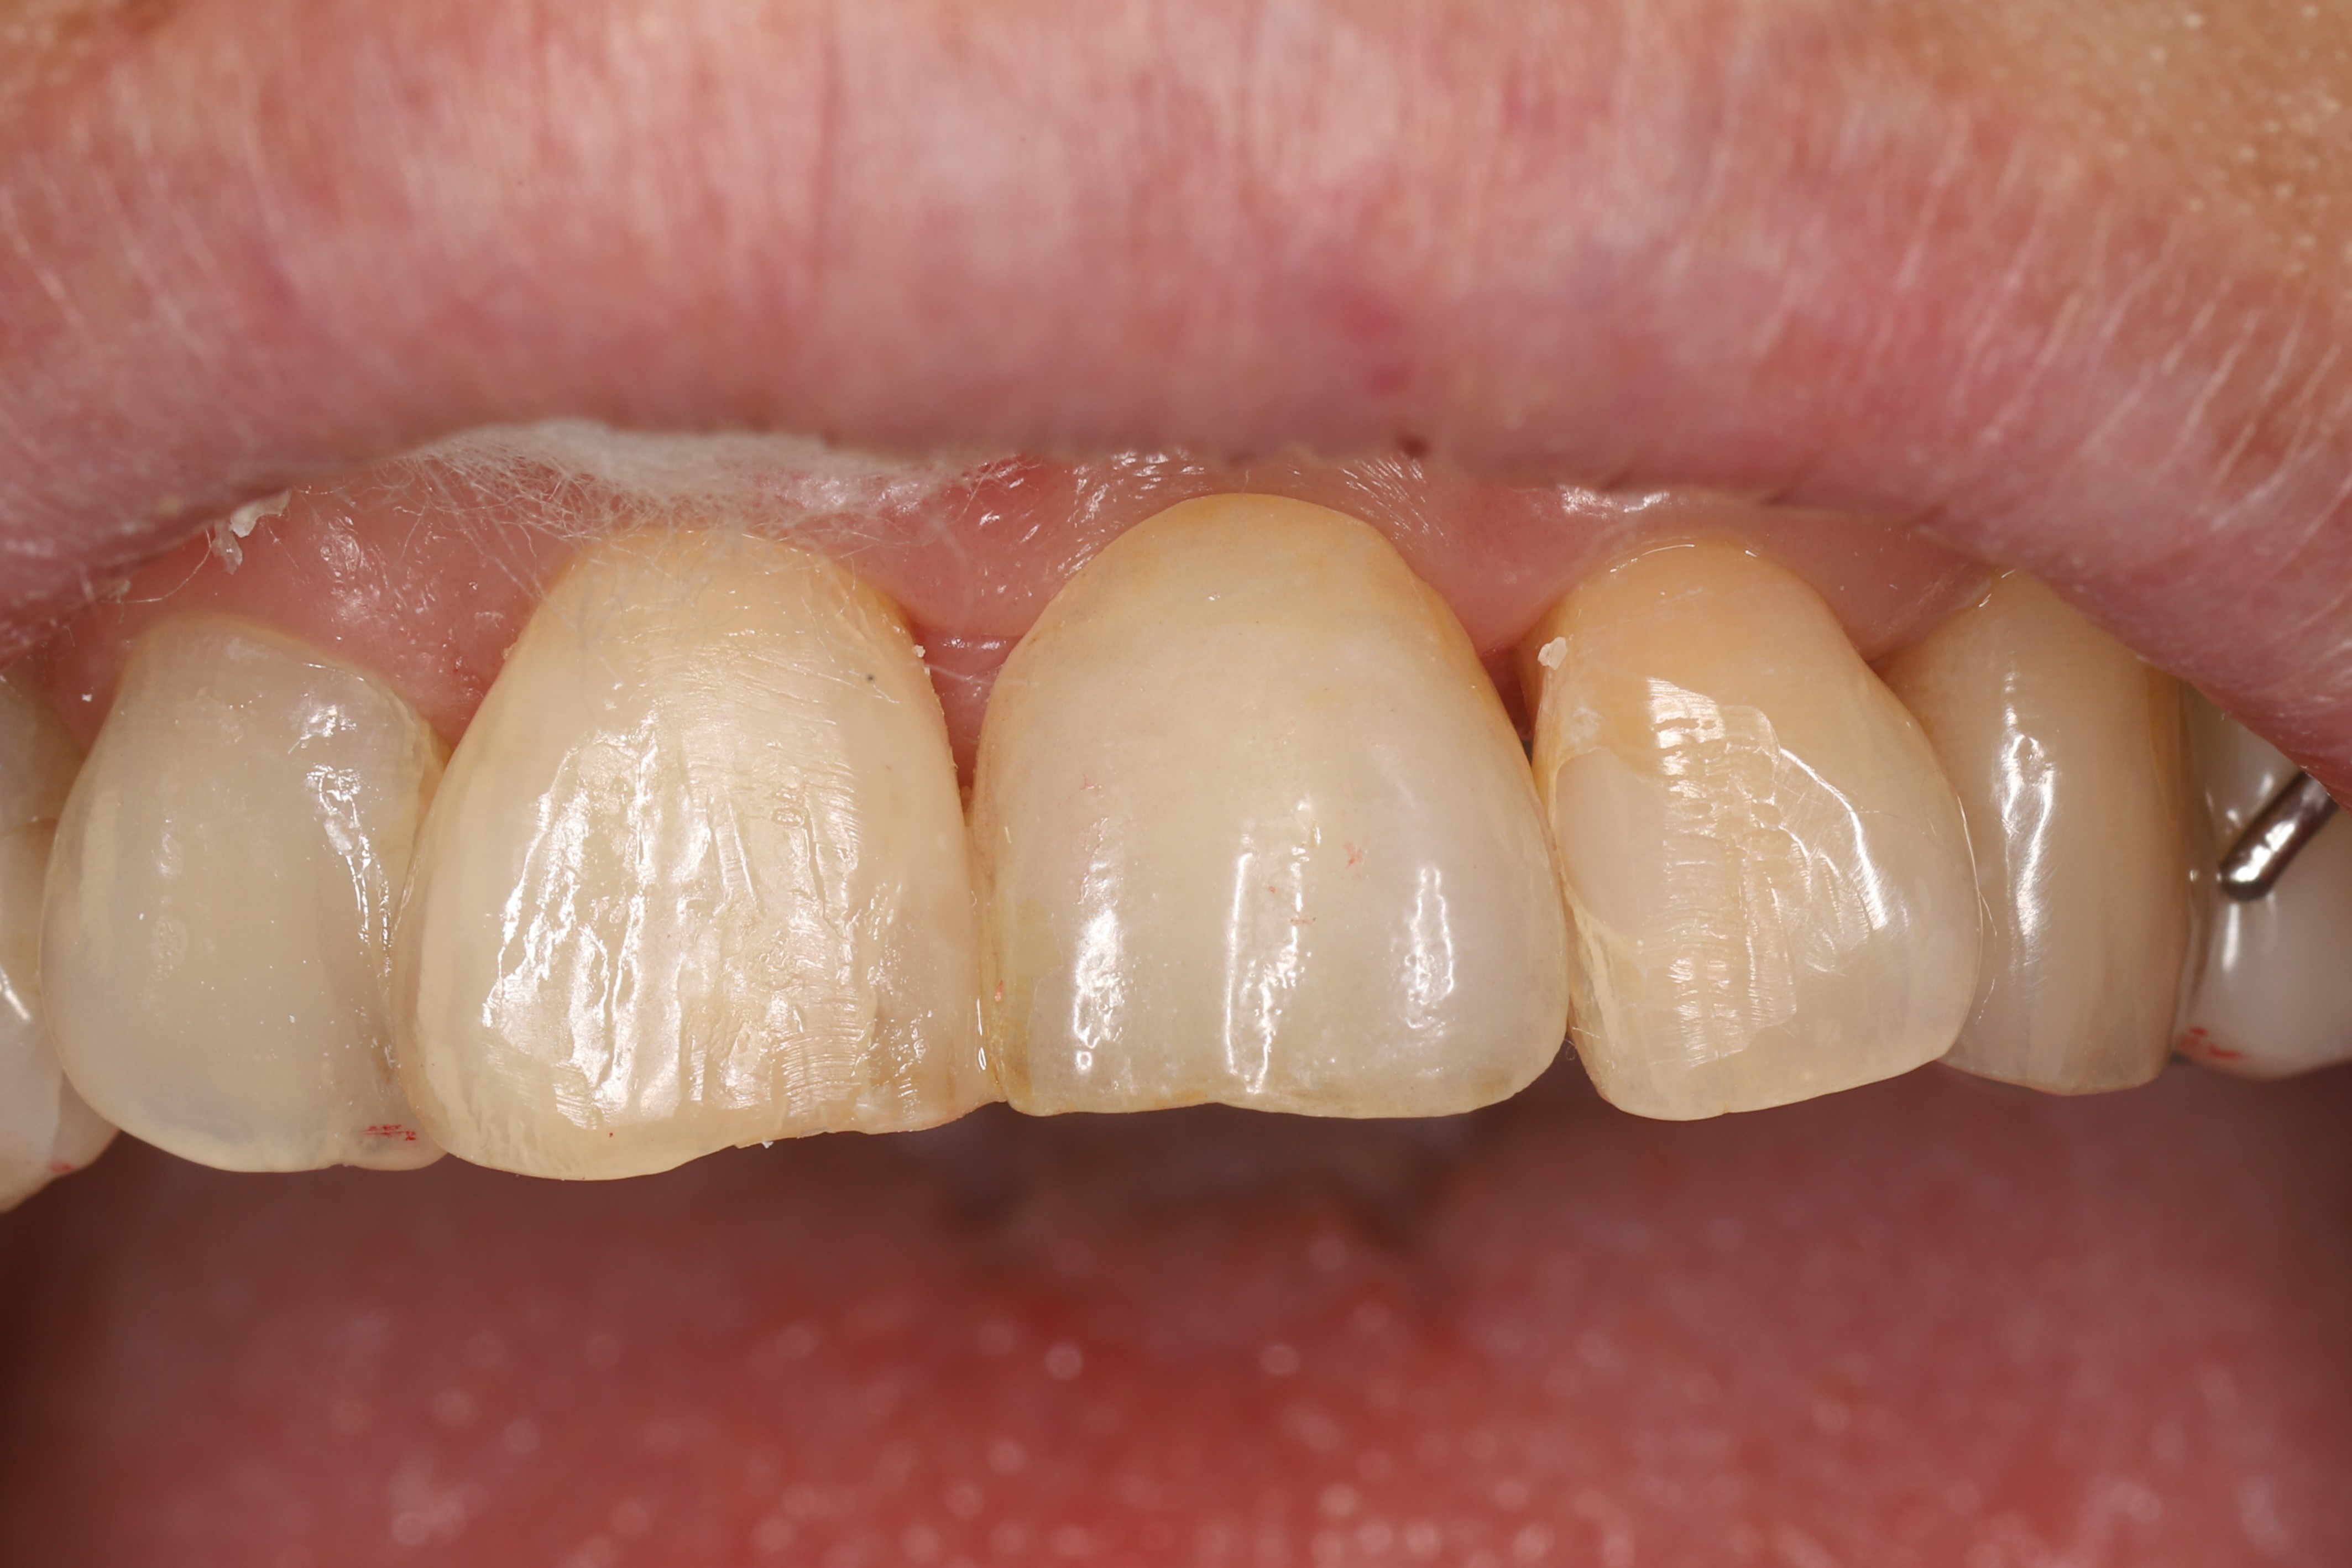

歯を抜いて歯茎が落ち着くまでの3ヶ月は仮歯で過ごします。画像は仮歯を外し、歯をセットする前の状態です。

【 歯セット後 】